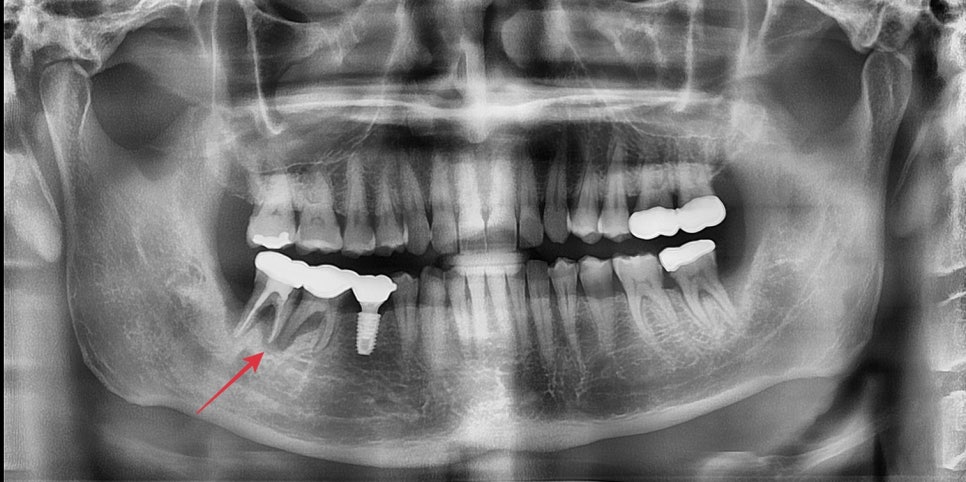

5달이 지난 어느날 내원해주셨는데

처음 내원때 사진보다 치아 주변 뼈가 더 많이 흡수가 되어있었습니다.

초기 진단과 다르게 임플란트가 들어가야할 공간에 뼈가 많이 흡수되어

치조골이식술을 한다해도 발치날 수술까지는 무리였습니다.

욕심내지 않고 주변 뼈의 볼륨을 회복 시킨후 수술하기로 했습니다.